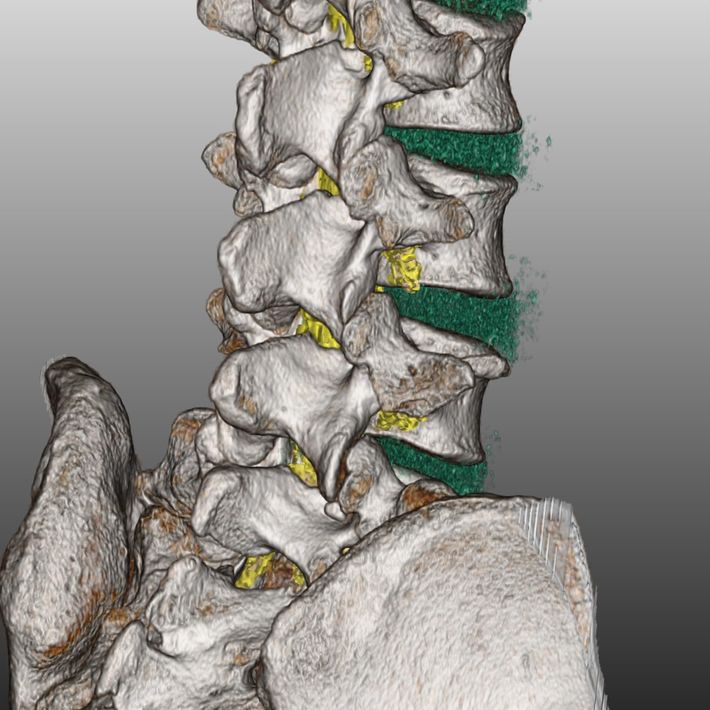

CTとMRIを融合した3D画像は、骨だけでなく椎間板や神経なども確認できるため手術をする際に作成される。(『

カニジル 18杯目

』より)